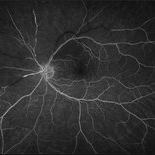

BRAO (3 files)

BRAO (3 files)

BRAO (3 files)

BRAO (3 files)